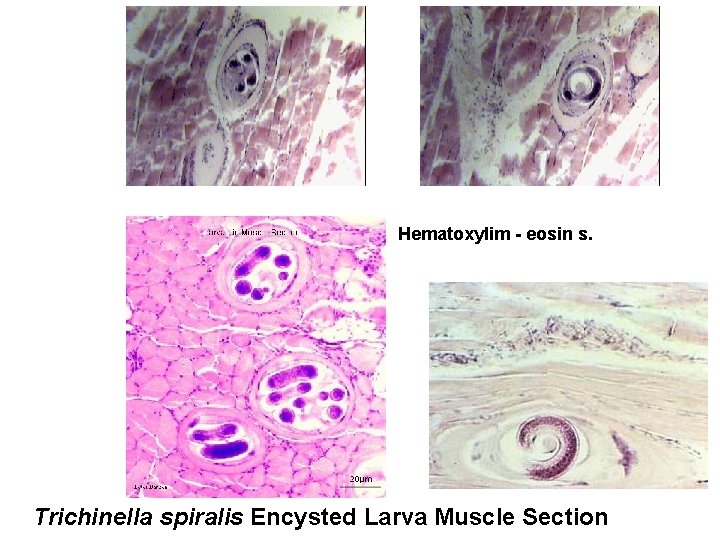

C-larva: spirally coiled within muscle fiber.

Hematoxylim - eosin s. Trichinella spiralis Encysted Larva Muscle Section